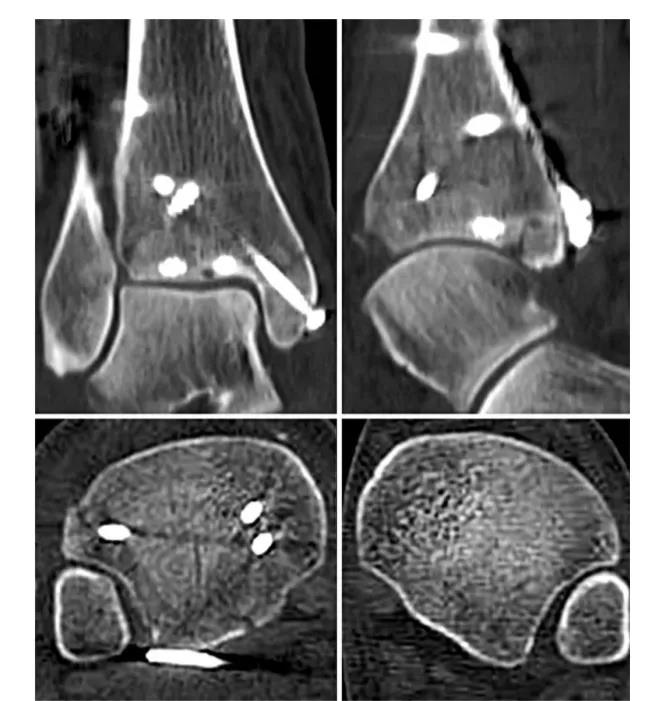

② 四踝骨折典型病例图。